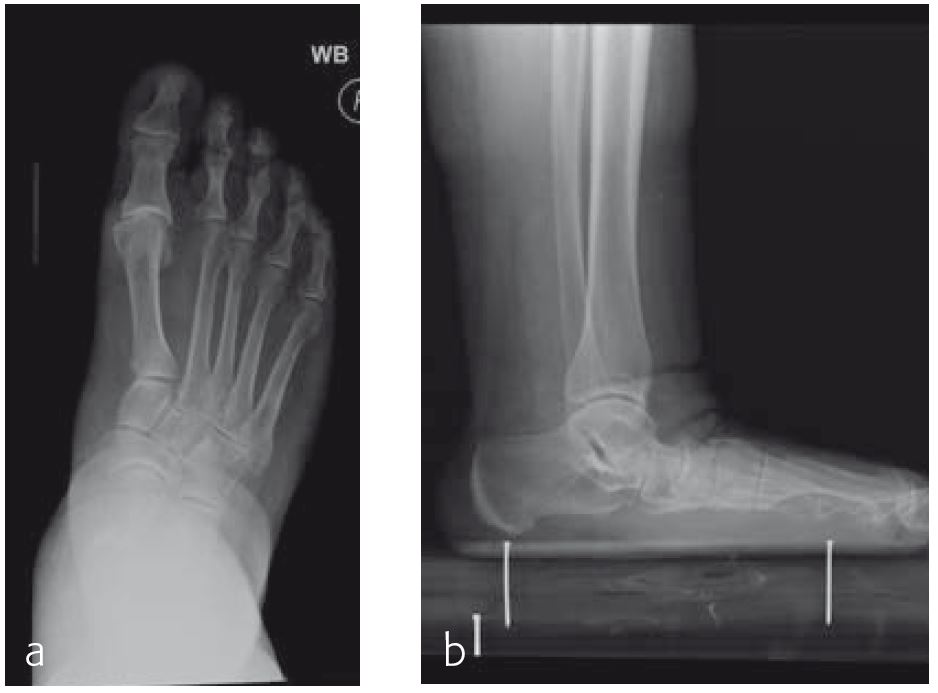

A 70-year-old female patient (Fig 1) had a long history of increasing painful deformity of her foot. She also noted increasing gait problems. There was no history of initial trauma. The examination showed severe rigid flatfoot deformity.

An extended triple arthrodesis was performed. Medially, the new Medial Column Plate was used, securing the talonavicular, naviculocuneiform, and tarsometatarsal joints (Fig 2). The X-plate is lateral and secured the calcaneo-cuboid joint. Two 7.3 mm screws were used to secure the subtalar joint.